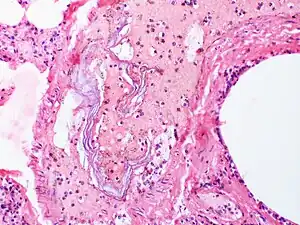

| Skin cells are present in the blood vessels of this case of amniotic fluid embolism. | |